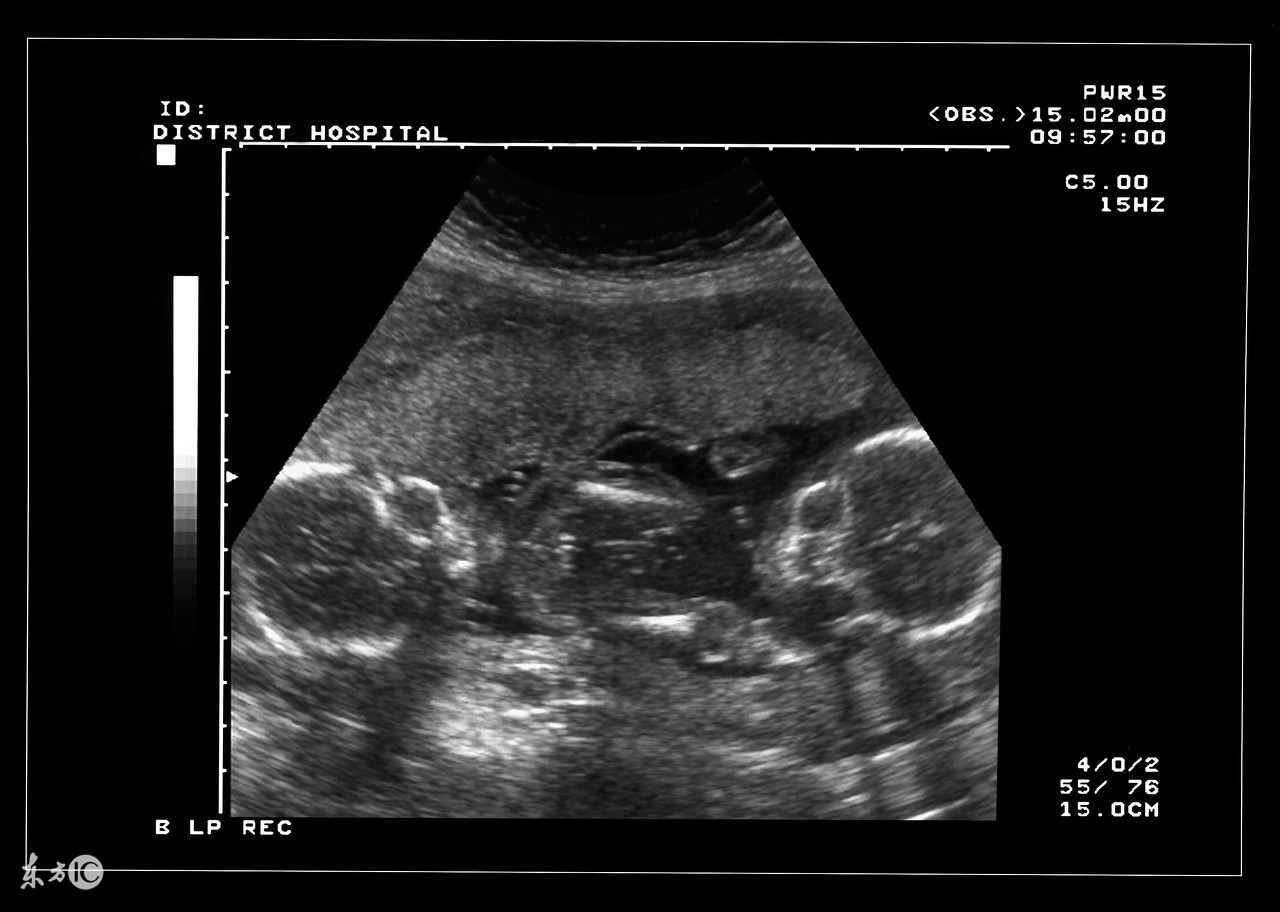

双胞胎确实是一件可想而不可求的事情,当孕妇怀上双胞胎或者多胎后,使母体长期处于超负荷的状态,在预产期到来之前,准妈妈需要就是否实施剖腹产的问题预先与家人和医生达成一致,并为此做好准备。大家都知道,自然分娩是最理想不过的,但实际上为了确保安全,大部分多胞胎最终实施的都是剖腹产。

双胎妊娠检查非常重要。由于双胎孕妇比一般孕妇子宫明显增大,这不仅增加了孕妇身体的负担,还由于对其心、肺及下腔静脉的压迫而容易产生心慌、呼吸困难及下肢浮肿等不适。双胎妊娠出现妊娠合并症者也较多,其妊高娠的发生率明显高于一胎妊娠,所以双胎妊娠者要听从医嘱,按期去医院接受检查。

双胎妊娠由于子宫腔相对狭窄胎盘血液循环障碍,其流产发生率较单胎妊娠高2—3倍,因此应加强孕期保护与监护。若一胎发生死胎,另一胎仍可继续生长发育,死亡的胎儿将被吸收或挤压成纸样儿随正常胎儿娩出,不必担心害怕,更不要引产终止妊娠。因双胎妊娠子宫过度膨胀,易发生早产,故应于中期妊娠后注意休息,避免房事,并提前4周做好分娩前的准备工作。由于妊娠的并发症尤其是妊高娠的发生率比较高,从母子安全考虑,应在预产期即住院待产,以免发生早产或其他不测。

如果是双胞胎,正常情况下可以自然分娩。通常每次只出生一个胎儿,下一个胎儿间隔一小时左右出生。而且,由于胎儿体形较单胞胎小一些,分娩也更加容易,痛苦不那么大。通常情况下,第一个胎儿会顺产,即头朝下进入产道,第二个方向相反,会屁股朝下,或者双脚先出来。比较麻烦的是横在产道口的,一般就必须实施剖腹产了。

多胞胎实施剖腹产的几率极高。在即将分娩时,由于胎儿处于活跃状态而相互拥挤,容易造成胎盘紧缩和脐带缠绕,严重时会对胎儿生命构成威胁,也令母亲极度痛苦。在这种情况下,就必须立即实施剖腹产。剖腹产手术时,麻醉师先实施局部麻醉,主刀医生会在孕妇的腹部横向或纵向划开一个口子,将子宫打开,把脐带剪断,将胎儿一个接一个地拿出来,然后缝合伤口。说起来简单,但是整个手术也需要好几个小时,而且在此期间也可能伴随着各种危险。